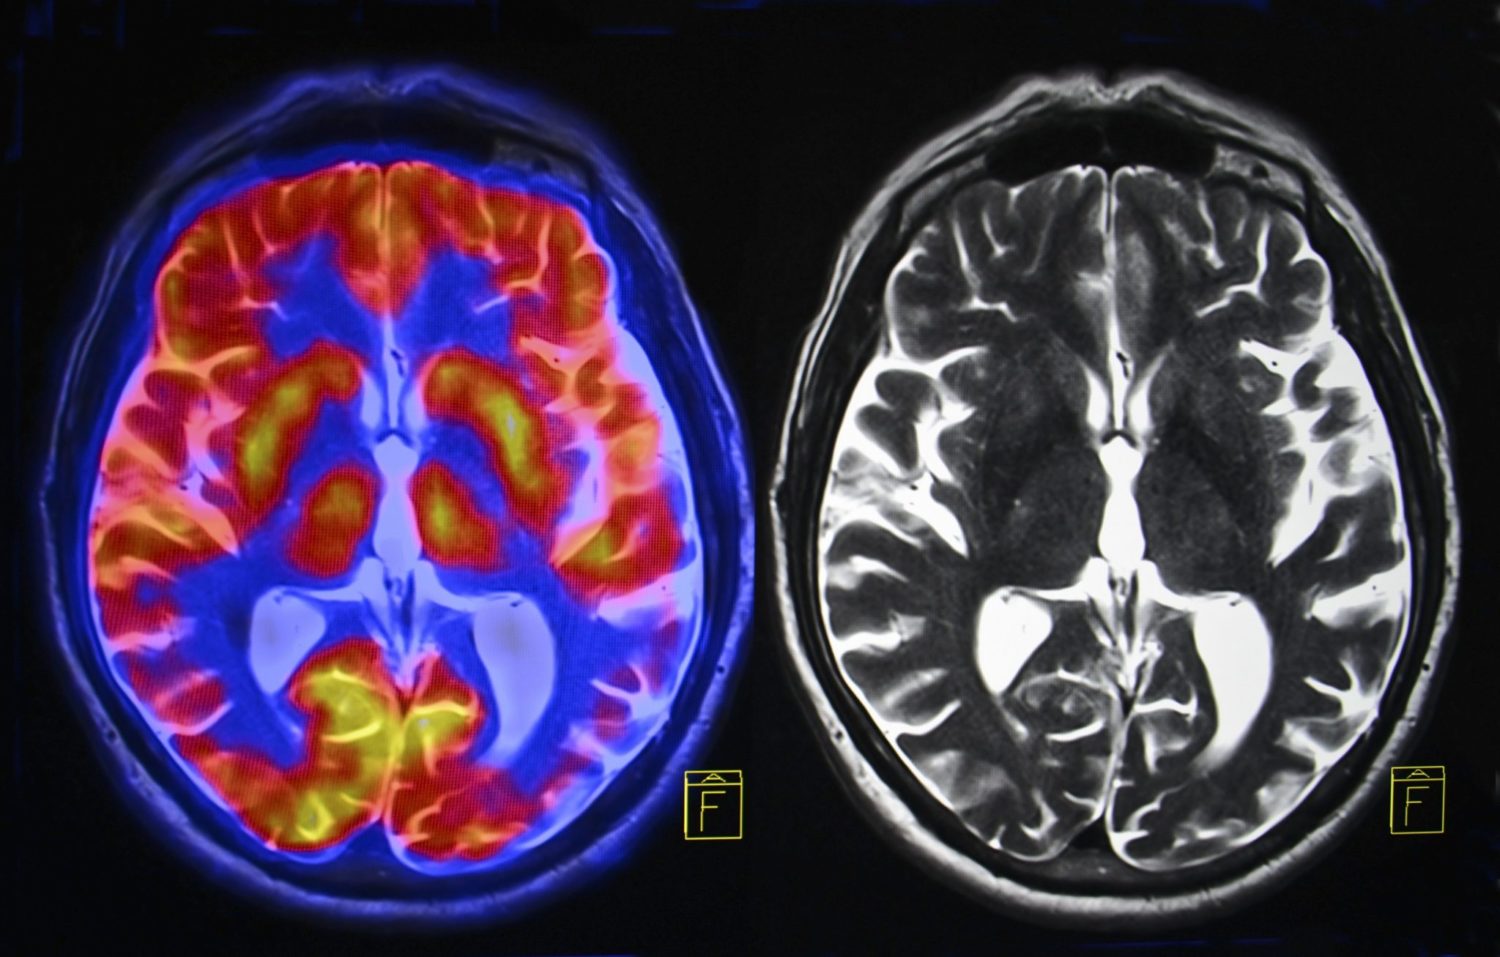

Estudios de imágenes cerebrales han comprobado que la cooperación, la reciprocidad y las recompensas sociales activan áreas como el estriado ventral donde se reciben grandes cantidades de dopamina.

Escáneres cerebrales indican que cuando un enamorado mira la foto de su pareja produce una fuerte activación de su circuito del placer, ¡segregando mucha dopamina!